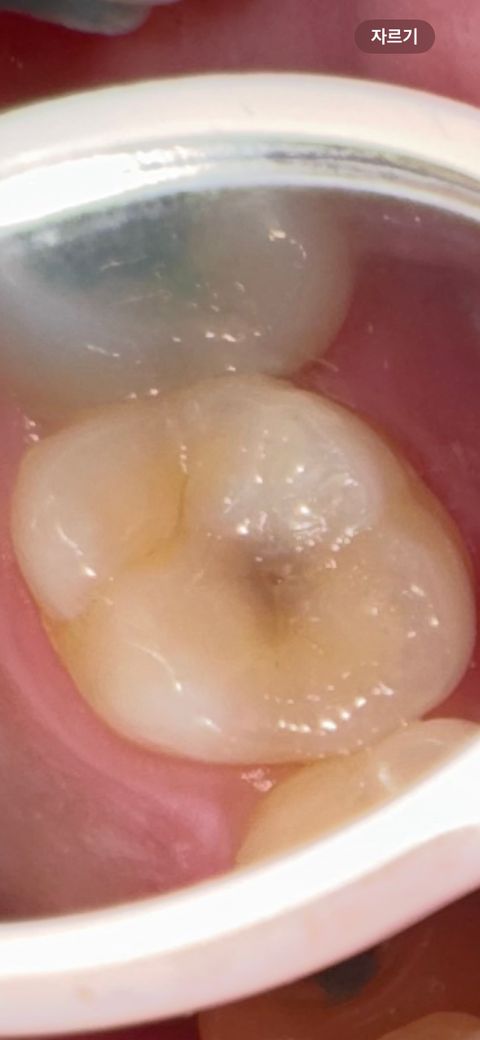

윗 어금니이구요 충치랑 크랙이 보이는데

레진으로 충치만 얘기하셔서요

크랙은 상관없을까요?

그리고 다른 의사선생님들이 볼 때에도 신경치료까지는 안해도 될까요 새벽에 불안한 마음에 올립니다

일단 충치범위가 커 보이지 않아 충치치료만 해도 될 것으로 보입니다. 신경치료 여부는 x-ray 보아야 진단할 수 있습니다.

충치는 잇어 보이는 크랙은 괜찮은거 같습니다 .충치가 깊을꺼 같으니 일단 엑스레이 촬영도 해보셔야될것같습니다 .

충치와 금이 같이 있는 치아라면 충치와 금을 제거하고 난 다음에 신경이 노출되지 않는지를 확인하는 것이 좋습니다. 신경이 노출이 된다면 신경치료가 필요하며 신경이 노출되지 않는다면 신경 치료를 하지 않고 보철 치료를 할 수도 있습니다.

자세한 확인을 위해서 치과에서 진료를 받아보는 것을 권유드립니다.

크랙이 깊지 않고 표면에만 있는 경우 크랙라인까지 확대하여 레진치료를 하는 경우도 있습니다